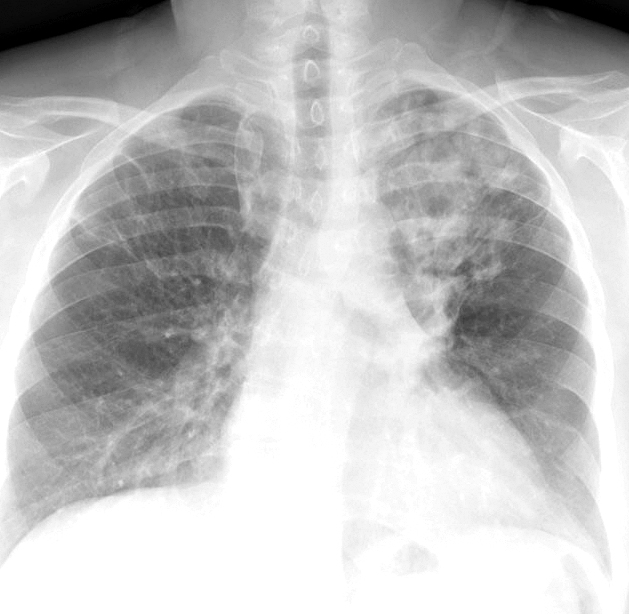

Gallery COPD more plugs

more plugs